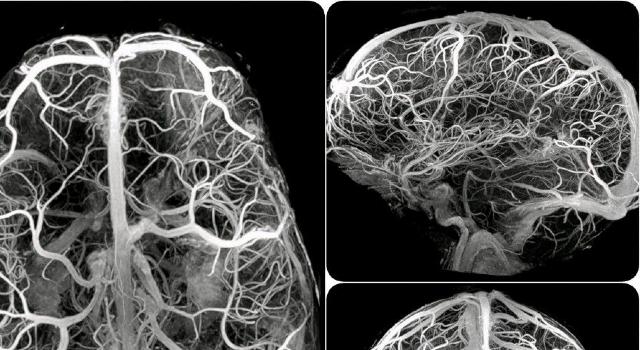

Artiria Medical is revolutionising neurovascular healthcare with cutting-edge minimally invasive medical technologies. Our first product, an innovative FDA-cleared wire with a micro-articulated seeking head, dramatically improves navigation through cerebral vessels to treat strokes. Current interventional devices lack control, leading to complications, increased costs and longer surgical procedures. Artiria's innovation improves precision, reduces risk and improves patient outcomes. Committed to excellence, Artiria is shaping the future of healthcare to help the 15 million people affected by stroke.